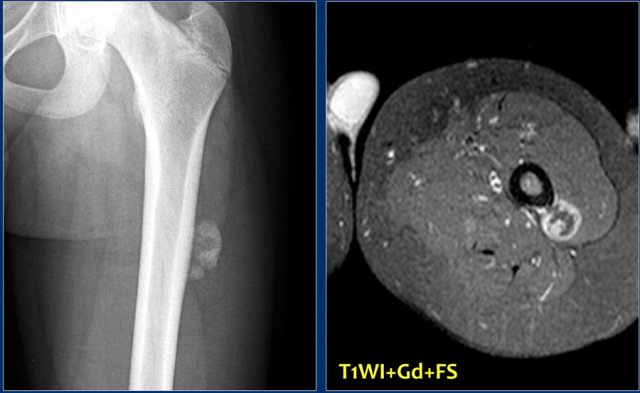

Study the images of another 14-year old patient and then continue reading.

The findings are:

• Radiograph.

Small homogeneous mass adjacent to the cortex of the diaphysis of the femur

• MRI

Juxtacortical mass with enhancement of the periphery.

Bone marrow and cortiical bone are otherwise normal.

Notice absence of reactive changes around the lesion.

Differential diagnosis:

1. Organized reactive post-traumatic mass like myositis ossificans.

2. Juxtacortical or Parosteal osteosarcoma, because of the homogeneity of the lesion.

Final diagnosis: parosteal osteosarcoma